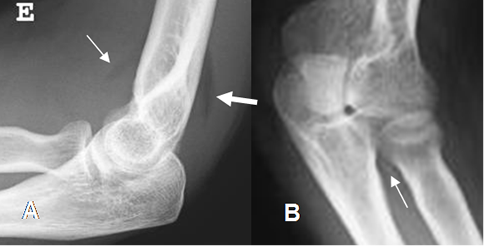

Para el Dx de estas lesiones también se utilizan los signos de la línea humeral anterior y la línea radiocapitelar.

La línea humeral anterior, normalmente pasa por el centro del núcleo de crecimiento del capitel, en niños mayores de 2.5 años. (13). En casos de fracturas, se produce desplazamiento posterior. (11). (Fig 29).

Fig 29. Signo de la línea humeral anterior en Rx lateral.

A: Línea normal, que cruza el capitel.

B: Fractura supracondilea con desplazamiento del capitel, que no es cruzado por la línea humeral anterior.

La línea radiocapitelar trazada por el eje del radio en la línea media, debe cruzar por el centro de capitel. En casos de fracturas, se desplaza. (13). (Fig 30).

Fig 30. Signo de la línea radiocapitelar en Rx lateral.

A: Línea normal, que cruza el centro del capitel.

B: Luxación del radio, con la línea cruzando la parte superior del capitel.